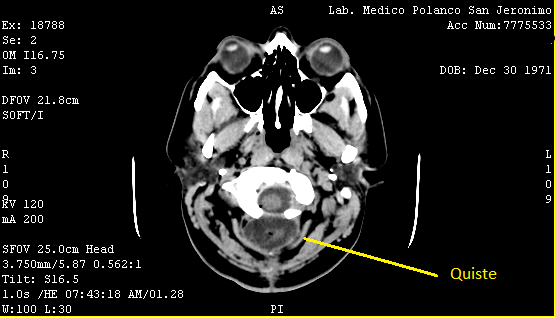

El doctor me pidió una tomografía: debido a mi historial quería asegurarse de que todo estuviera bien. En el estudio salió que tenía un poco de agua y aire, pero consideraba que eran cambios postquirúrgicos. Lo que no le gustaba eran las temperaturas que no cedían y que los dolores de cabeza iban en aumento, así que me citó en el hospital únicamente para tomar una muestra del agua y descartar que fuera resultado de una nueva infección.

El 30 de octubre me presenté en Urgencias para una punción en la cabeza. El procedimiento era muy simple: extrajeron el líquido que se veía acumulado en la tomografía, justo en la cicatriz y lo mandaron al laboratorio. Me dijo que podía irme a casa y que en cuanto tuviera el resultado de la biopsia, me llamaría. Todo el día estuve relativamente estable con temperaturas y dolores, pero en la madrugada al levantarme para ir al baño, perdí la conciencia otra vez. A ciencia cierta, no sé cuánto tiempo estuve tirada en el piso, pero cuando desperté me habían regresado los temblores del cuerpo y la mano, y no podía ni sentarme en el excusado, por lo que me costó mucho trabajo incorporarme.